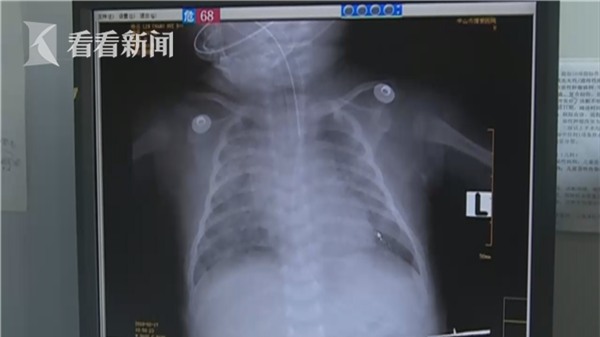

Bác sĩ Lý ở bệnh viện này cho biết, cả 2 bệnh nhi đều nhập viện trong tình trạng thiếu khí oxy, sắc mặt trắng bệch, hơi thở yếu. Trong đó có 1 bé tên Đông Đông, mới 39 ngày tuổi, được người nhà phát hiện có dấu hiệu tứ chi tê cứng, toàn thân tím tái trong lúc bé đang ngủ say.

Trường hợp của 2 bệnh nhi này cũng tương tự như vậy, nhiều cơ quan nội tạng bao gồm phổi, tim và thận đều bị rối loạn chức năng. 2 cơ quan trọng điểm là tim và phổi đều đã hồi phục, chức năng não cũng tạm ổn, chỉ còn thận là phục hồi khá chậm. Hiện tại, bé vẫn không có nước tiểu và có thì là tiểu ra máu.

May mắn là ý thức của Đông Đông đã trở nên tỉnh táo nhưng vẫn chưa thoát khỏi nguy hiểm về tính mạng còn bệnh nhi còn lại, bé Tiểu Trân thì tình hình nghiêm trọng hơn. Vì tình trạng ngạt thở, thiếu oxy kéo dài hơn 5 tiếng mới được phát hiện nên nhiều cơ quan nội tạng của Tiểu Trân đã bị suy kiệt chức năng.